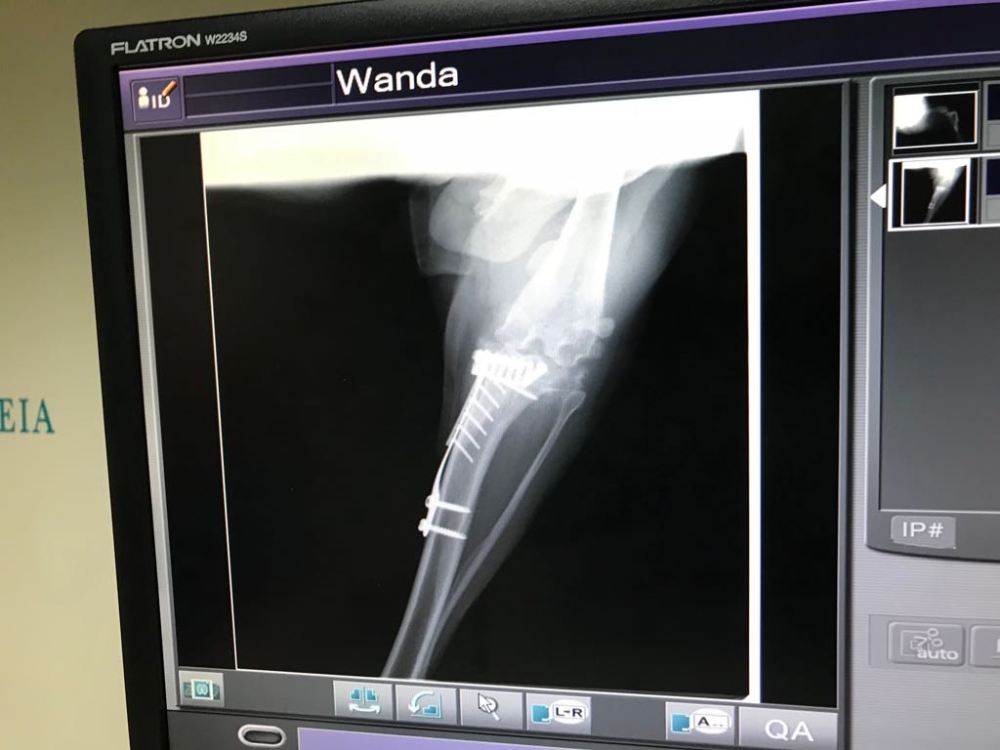

Pochi secondi di immobilità assoluta. E la ferramente appare in tutto il suo splendore sullo schermo.

Prima radiografia, tutto bene per quello che ho avuto dice il vet. Ci rivediamo fra un mese e mezzo per un’altra radiografia.